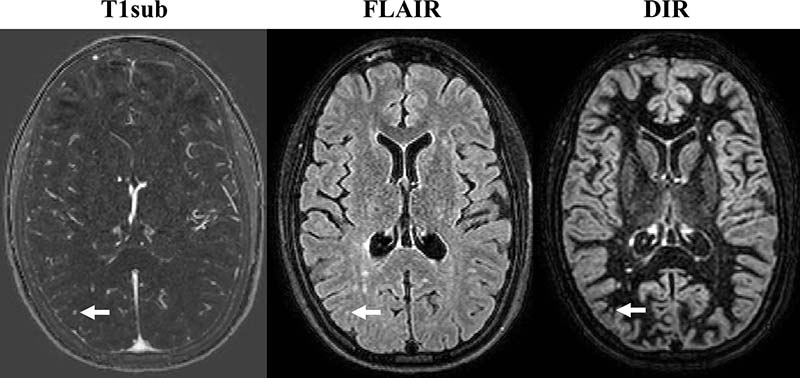

Axial MR images obtained in 32-year-old woman with relapsing-remitting multiple sclerosis. Images were obtained with subtraction of unenhanced T1-weighted MR image from contrast-enhanced MR image (T1sub), fluid-attenuated inversion recovery (FLAIR), and double inversion recovery (DIR). The new lesion (arrow), a small, subcortical lesion in right parietal lobe, is seen only on contrast-enhanced image; it was overlooked on DIR and FLAIR images. Note that there are several other new or enlarged lesions that can be seen on nonenhanced images.